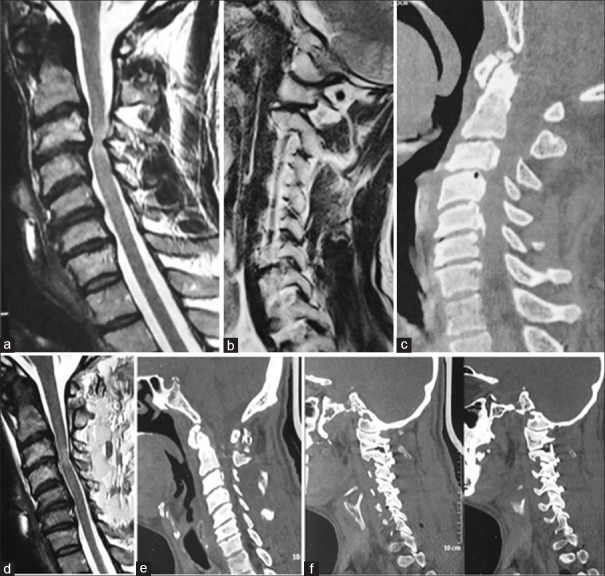

Figure 1.

Images of a 40-year-old male. (a) T2-weighted magnetic resonance imaging showing evidence of multilevel spinal cord compression by osteophytes and buckled ligamentum flavum. (b) Computed tomography scan showing no evidence of atlantoaxial instability. (c) Magnetic resonance imaging cut passing through the facets showing type 2 atlantoaxial facetal instability. (d) Postoperative computed tomography scan. No bone decompression is seen. (e) Computed tomography scan cut passing through the facets showing C1-2, 2-3, 3-4, 4-5, and 5-6 fixation. (f) Postoperative magnetic resonance imaging 6 months after the surgery shows reduction in the extent of neural compression by the osteophytes and bulging ligamentum flavum